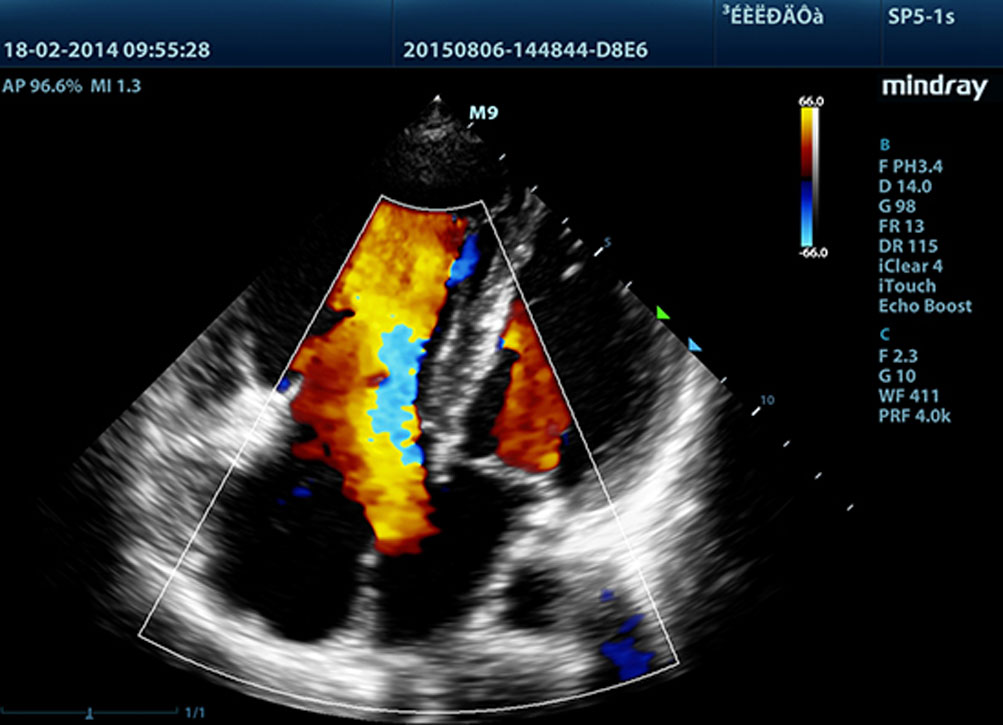

3T Transducer Technology with Single Crystal

Providing sharper images, all probes compatible with the M9 come equipped with MindrayŌĆÖs unique 3T transducer technology. Enhanced with the addition of single crystal technology, M9 offers better penetration and color dynamic flow, especially during difficult-patient scanning.

Echo Boost?

MindrayŌĆÖs unique adaptive signal processing technology with intelligent echo detection, designed to utilize the native signal-to-noise information to enhance the weak echo signals while suppressing the surrounding clutter noise, providing more balanced image brightness and improved visualization of myocardium tissue layers.